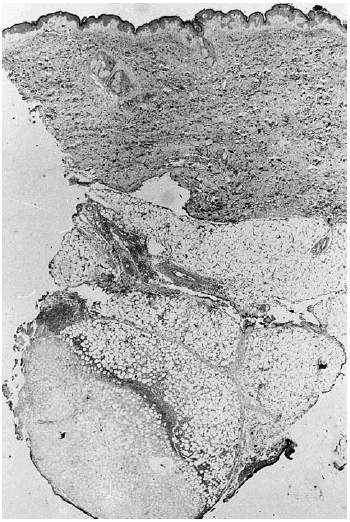

A los pocos días le apareció una lesión nodular dolorososa en el costado, de 6 cm de diámetro, de superficie eritematosa y crecimiento rápido. Se realizó biopsia cutánea, enviando muestra para cultivo y para estudio histopatológico. En el cultivo se identificó Aspergillus flavus y el examen histológico mostraba en piel una lesión centrada en el tejido celular subcutáneo (fig. 1) donde se observaba un área de necrosis amplia de los lobulillos adiposos (figs. 2 y 3), en cuyo interior se reconocían abundantes nidos de hifas fúngicas tabicadas, positivas con las tinciones de PAS y metenamina plata.

Fig. 2.--Área de necrosis del tejido adiposo donde se observan en la zona periférica hifas de Aspergillus.

Fig. 3.--Detalle de la figura anterior en la que se reconocen claramente las hifas de Aspergillus distribuidas difusamente en el área de necrosis.